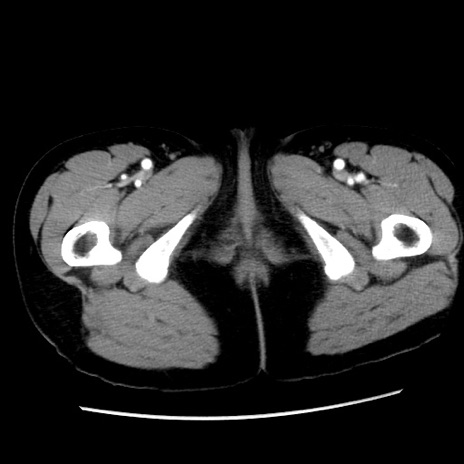

症例10(横断像)

【症例】 50歳代女性

【主訴】 腹痛

【現病歴】前日生レバーを食べた。今朝に排便あり。 昼前に突然発症の腹痛を生じ、当院救急外来を受診した。

【身体所見】 意識清明、腹部:平坦、軟、下腹部やや左を中心に圧痛・反跳痛あり、筋性防御あり